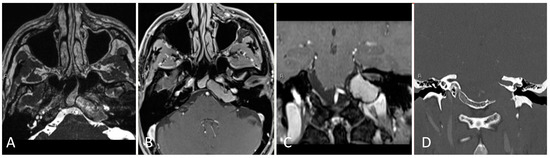

3.2.2. Illustrative Case